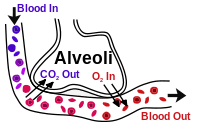

Gas Exchange

Gas exchange in the lungs and in the alveoli is between the alveolar air and the blood in the pulmonary capillaries. This exchange is a result of increased concentration of oxygen, and a decrease of C02. This process of exchange is done through diffusion.

External Respiration

External respiration is the exchange of gas between the air in the alveoli and the blood within the pulmonary capillaries. A normal rate of respiration is 12-25 breaths per minute. In external respiration, gases diffuse in either direction across the walls of the alveoli. Oxygen diffuses from the air into the blood and carbon dioxide diffuses out of the blood into the air. Most of the carbon dioxide is carried to the lungs in plasma as bicarbonate ions (HCO3-). When blood enters the pulmonary capillaries, the bicarbonate ions and hydrogen ions are converted to carbonic acid (H2CO3) and then back into carbon dioxide (CO2) and water. This chemical reaction also uses up hydrogen ions. The removal of these ions gives the blood a more neutral pH, allowing hemoglobin to bind up more oxygen. De-oxygenated blood "blue blood" coming from the pulmonary arteries, generally has an oxygen partial pressure (pp) of 40 mmHg and CO2 pp of 45 mmHg. Oxygenated blood leaving the lungs via the pulmonary veins has an O2 pp of 100 mmHg and CO2 pp of 40 mmHg. It should be noted that alveolar O2 pp is 105 mmHg, and not 100 mmHg. The reason why pulmonary venous return blood has a lower than expected O2 pp can be explained by "Ventilation Perfusion Mismatch".

There are a number of terminal bronchioles connected to respiratory bronchioles which then advance into the alveolar ducts that then become alveolar sacs. Each bronchiole terminates in an elongated space enclosed by many air sacs called alveoli which are surrounded by blood capillaries. Present there as well, are Alveolar Macrophages, they ingest any microbes that reach the alveoli. The Pulmonary Alveoli are microscopic, which means they can only be seen through a microscope, membranous air sacs within the lungs. They are units of respiration and the site of gas exchange between the respiratory and circulatory systems.

Cellular Respiration

First the oxygen must diffuse from the alveolus into the capillaries. It is able to do this because the capillaries are permeable to oxygen. After it is in the capillary, about 5% will be dissolved in the blood plasma. The other oxygen will bind to red blood cells. The red blood cells contain hemoglobin that carries oxygen. Blood with hemoglobin is able to transport 26 times more oxygen than plasma without hemoglobin. Our bodies would have to work much harder pumping more blood to supply our cells with oxygen without the help of hemoglobin. Once it diffuses by osmosis it combines with the hemoglobin to form oxyhemoglobin.